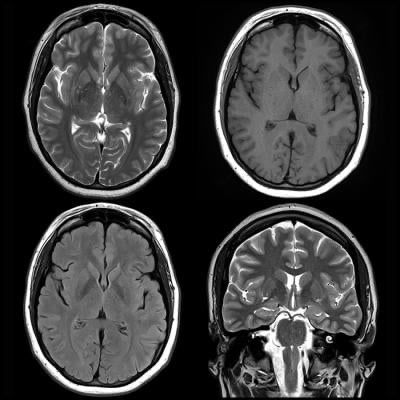

Featured image is from January 2, 2018 — “Information from brain magnetic resonance images (MRIs) can help identify people wi

Featured image is from January 2, 2018 — “Information from brain magnetic resonance images (MRIs) can help identify people with attention deficit hyperactivity disorder (ADHD) and distinguish among subtypes of the condition, according to a study appearing online in the journal Radiology.”